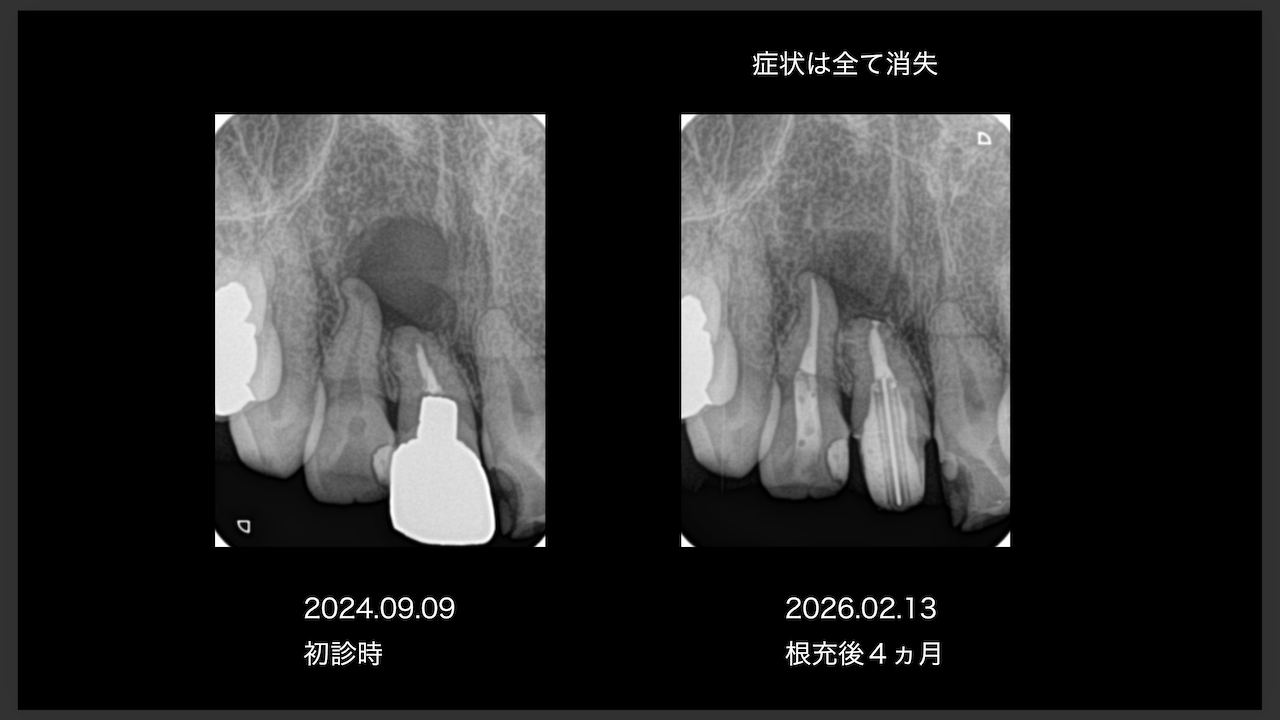

ここから4ヶ月が経過すると…

臨床症状も皮質骨も大きく治癒している。

1年後の予後が気になるところであるが、すごくよくマネージメントできているだろう。